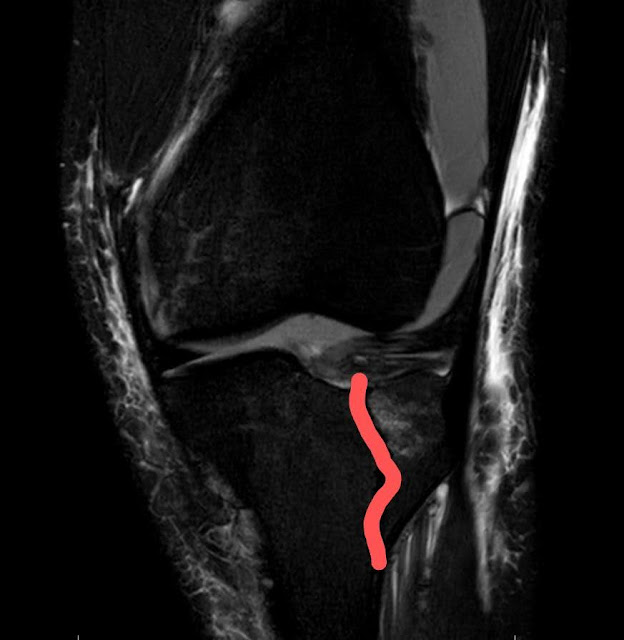

I was referred to an Orthopedic Surgeon who confirmed with MRI (imaged below) that both legs were fractured. On Thursday 08/06/2020, I went into surgery and had three screws placed in each leg, holding the fracture together to heal faster.